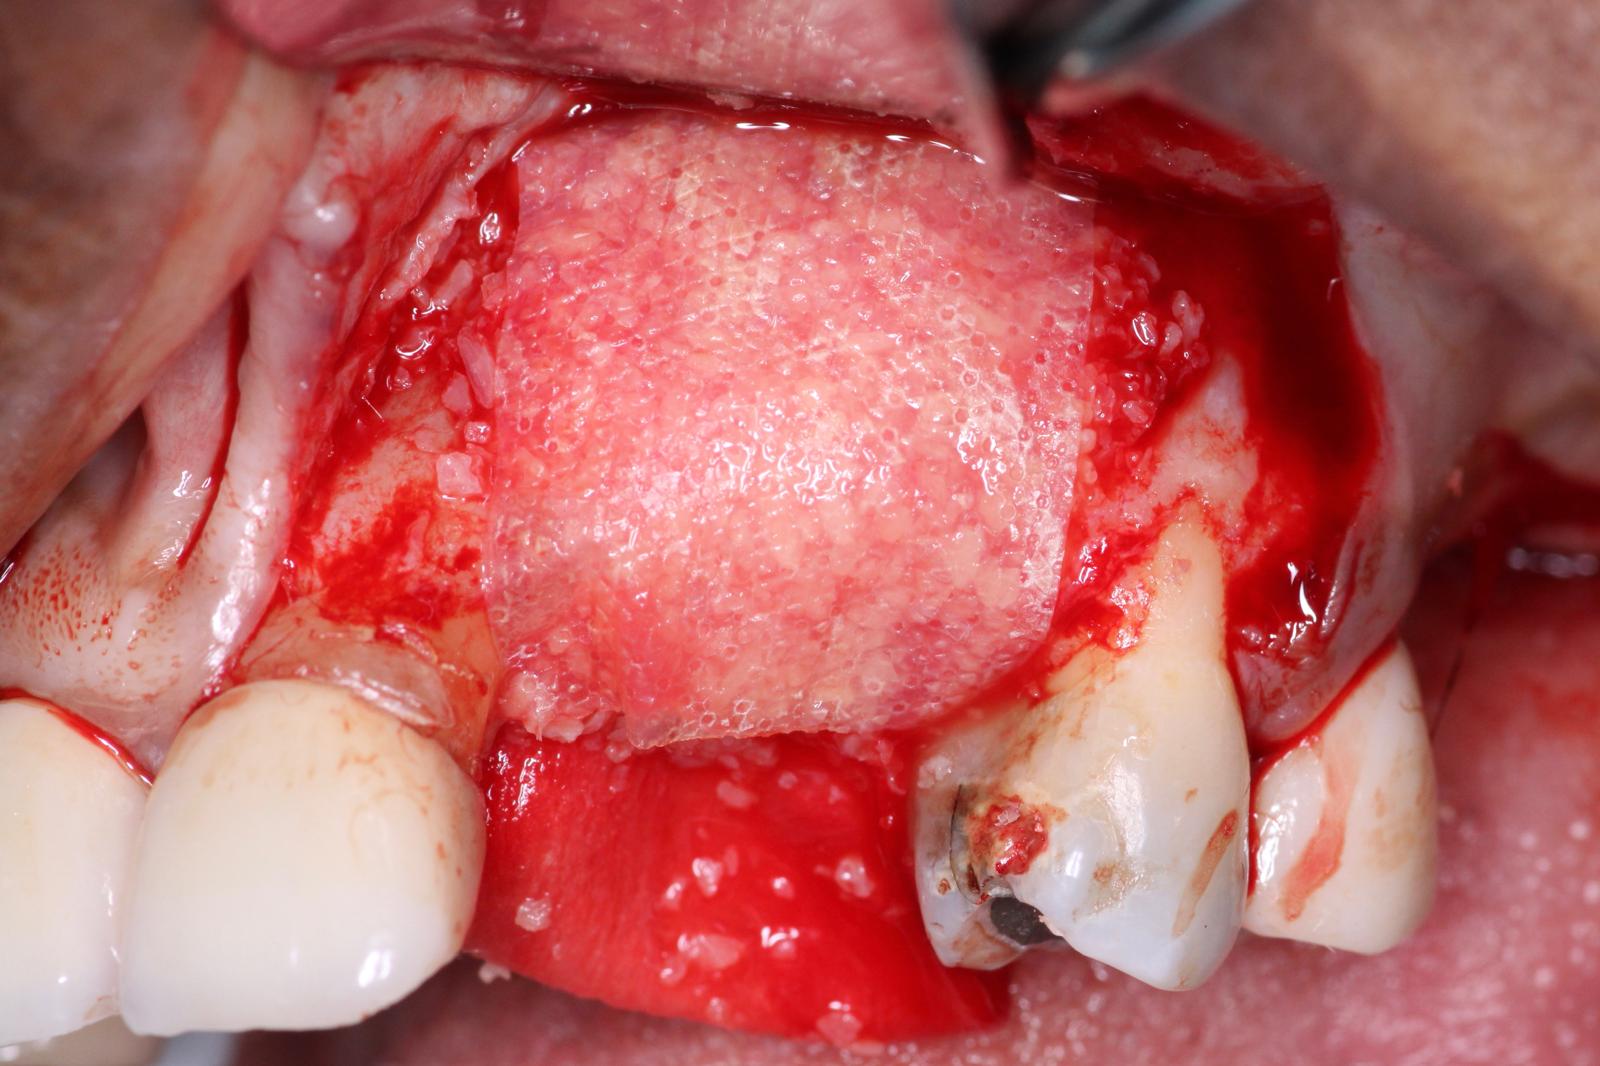

The first part of our grafting technique involved placement of DALI Cortical Cancellous Graft and initial placement of OsseoSeal Collagen Membrane. Notice how we position the membrane to tuck it under the palatal flap to help build up the bone graft. (for additional information on this technique see: Placement Techniques for OsseoSeal Porcine Collagen Membrane and Using OsseoSeal for Buccal Contour Augmentation )